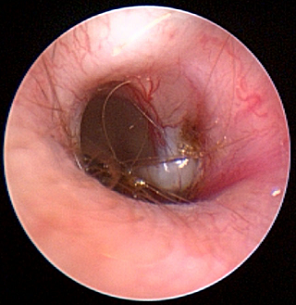

• myringotomy

Treatment

primarily has consisted of performing a myringotomy

(see photo at right), making a small cut in the eardrum (tympanic

membrane), followed by flushing the middle ear to force out the mucus

plug. The photograph at right is of a myringotomy in progress. The ring

in the middle of the photo is the eardrum. The tube tip at the top is

the device used to flush the inner ear and force out the mucus. You may

watch a

Treatment

primarily has consisted of performing a myringotomy

(see photo at right), making a small cut in the eardrum (tympanic

membrane), followed by flushing the middle ear to force out the mucus

plug. The photograph at right is of a myringotomy in progress. The ring

in the middle of the photo is the eardrum. The tube tip at the top is

the device used to flush the inner ear and force out the mucus. You may

Following the myringotomy, the specialist typically will repeat the CT scan, to see if all of the mucus has been removed, and then a BAER test to determine if hearing has been restored. Topical and/or systemic corticosteroids and antibiotics then are administered. The procedure may have to be repeated periodically, in some cases several times, depending upon how the dog responds.